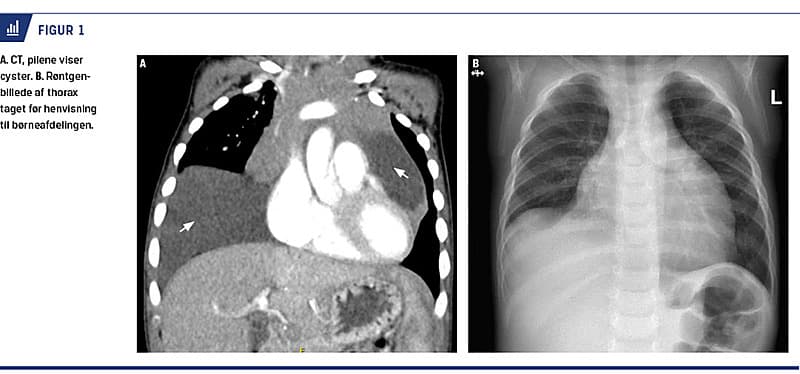

En røntgenoptagelse af thorax gav mistanke om et stort hjerte, der fyldte det meste af venstre thoraxhalvdel. Elektrokardiogrammet var normalt for patientens alder. En efterfølgende transtorakal ekkokardiografi viste en cystisk masse i den højre kardiofreniske vinkel med nær relation til perikardiet, hvilket dislokerede hjertet. En CT af thorax viste to store cyster indeholdende talrige septae i mediastinum (Figur 1). Den ene cyste (10,3 × 2,4 cm) displacerede thymus og omgav perikardiet. Den anden cyste (13,6 × 9,2 cm) strakte sig ind i højre hemithorax og komprimerede trachea i niveau med carina trachea. De tentative diagnoser efter CT var perikardiecyste, thymuscyste eller lymfangiom.